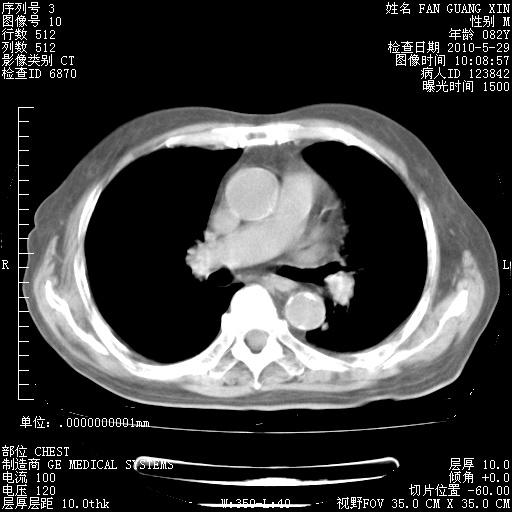

还需要哪些辅助检查?我们医院排除真菌感染没有任何检验方法,胸片好像能够排除肺部真菌感染。

补充:ENA化验全部阴性。免疫五项(IgG、IgA、IgM、C3、C4)只有C4略高。

CD3+ T细胞/淋巴细胞 46% (参考值50.00~84.00%)

CD3+CD4+ T细胞/淋巴细胞 21% (参考值27.00~51.00%)

CD3+CD8+ T细胞/淋巴细胞 25% (参考值15.00~44.00%)

CD3+CD4+ T细胞/CD3+CD8+ T细胞 0.84 (参考值0.71~2.78)

T细胞亚群是治疗5天采血。